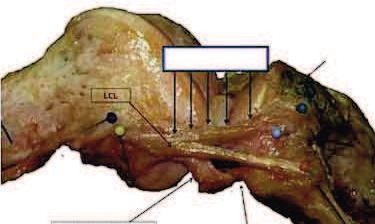

Hikka waɗi ɗum noon duuɓi 134 ko o haalnoo ɗum. Jooni kadi, doktoreeɓe ɓee, ngam yiytude ɗum, ɓe ceekii koppi 41 maayɗo, tee ɓe kuutorii karallaagal hutto (kuttugol) keeringal. A ɓe njenanaa wonde ngelɗoo ɓoggel raɗo ina woodi e koppi yimɓe fof (97% koppi). E miijo maɓɓe, ngalɗoo ganndal kesal maa addan ɓe waawde safrude koppi pokkiiɗi, sibu ina teskanoo hofru ina saɗtunoo safrude haa sella tawa alaa ko heddii. Raɗoyel ngel woni ko sawndo yeeso hofru. Ina gasa kadi raɗoyel ngel innirii doktoor Segond.